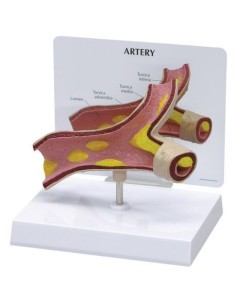

Indispensables aux étudiants comme aux professionnels, nos modèles anatomiques sont des outils pédagogiques qui permettent d'observer les structures anatomiques avec précision, en évitant les dissections ou les études invasives. Ils sont également utiles pour expliquer les pathologies aux patients, ce qui rend la communication plus efficace et permet de gagner un temps précieux.